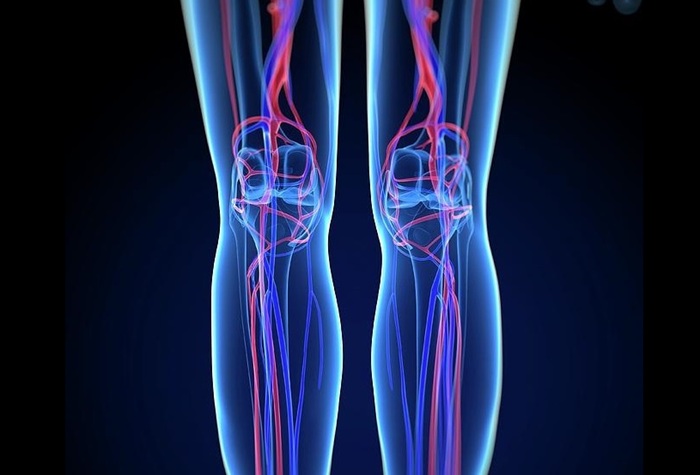

По результатам МР-ангиографии сосудов нижних конечностей получаются черно-белые изображения с очертаниями ног, внутри которых расположены подсвеченные артерии, вены и менее крупные их ответвления. На сканерах высокого разрешения можно различить даже микроскопические капилляры. Кости и соседние мягкие ткани отходят на второй план, ветви кровеносной сети становятся более светлыми и контрастными, что позволяет изучить их строение и найти патологии.